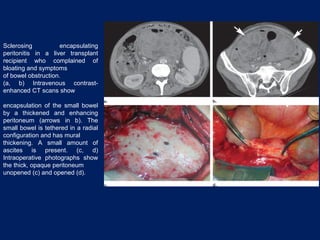

3- Sclerosing Encapsulating Peritonitis

•A rare chronic inflammatory disorder of the peritoneum that occurs

in patients who undergo continuous ambulatory peritoneal dialysis.

•It may also be idiopathic, associated with ventriculoperitoneal

shunts, liver transplantation, tuberculosis, foreign material, and use

of beta-blocker drugs (as a rare complication).

CT:

•Diffusely thickened peritoneum, ascites; small bowel may be tethered or

matted within loculated fluid collections.

•Multiple foci of linear calcification may develop as the disease progresses.

Sclerosing encapsulating

peritonitis in a liver transplant

recipient who complained of

bloating and symptoms

of bowel obstruction.

(a, b) Intravenous contrast-

enhanced CT scans show

encapsulation of the small bowel

by a thickened and enhancing

peritoneum (arrows in b). The

small bowel is tethered in a radial

configuration and has mural

thickening. A small amount of

ascites is present. (c, d)

Intraoperative photographs show

the thick, opaque peritoneum

unopened (c) and opened (d).